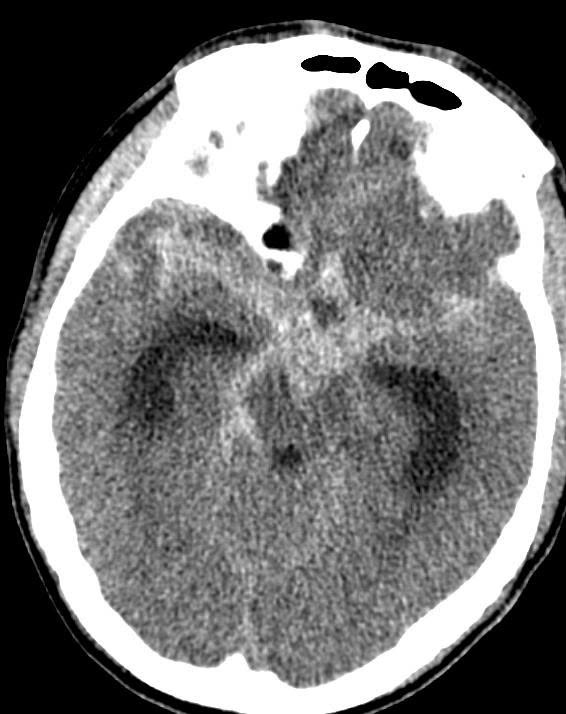

Phình mạch não là sự giãn khu trú bất thường của một động mạch não, là hậu quả của thiếu lớp cơ trong của thành mạch máu. Thành mạch yếu, giãn phình ra và trở nên mỏng, phát triển có thể dẫn đến vỡ đột ngột mà không báo trước, gây xuất huyết dưới nhện (SAH) – một biến cố nguy hiểm tính mạng, để lại di chứng nặng nề hoặc tử vong.

– Tỷ lệ tử vong khi phình mạch não vỡ có thể lên tới 30–40%, nhiều người sống sót vẫn mang di chứng lâu dài.